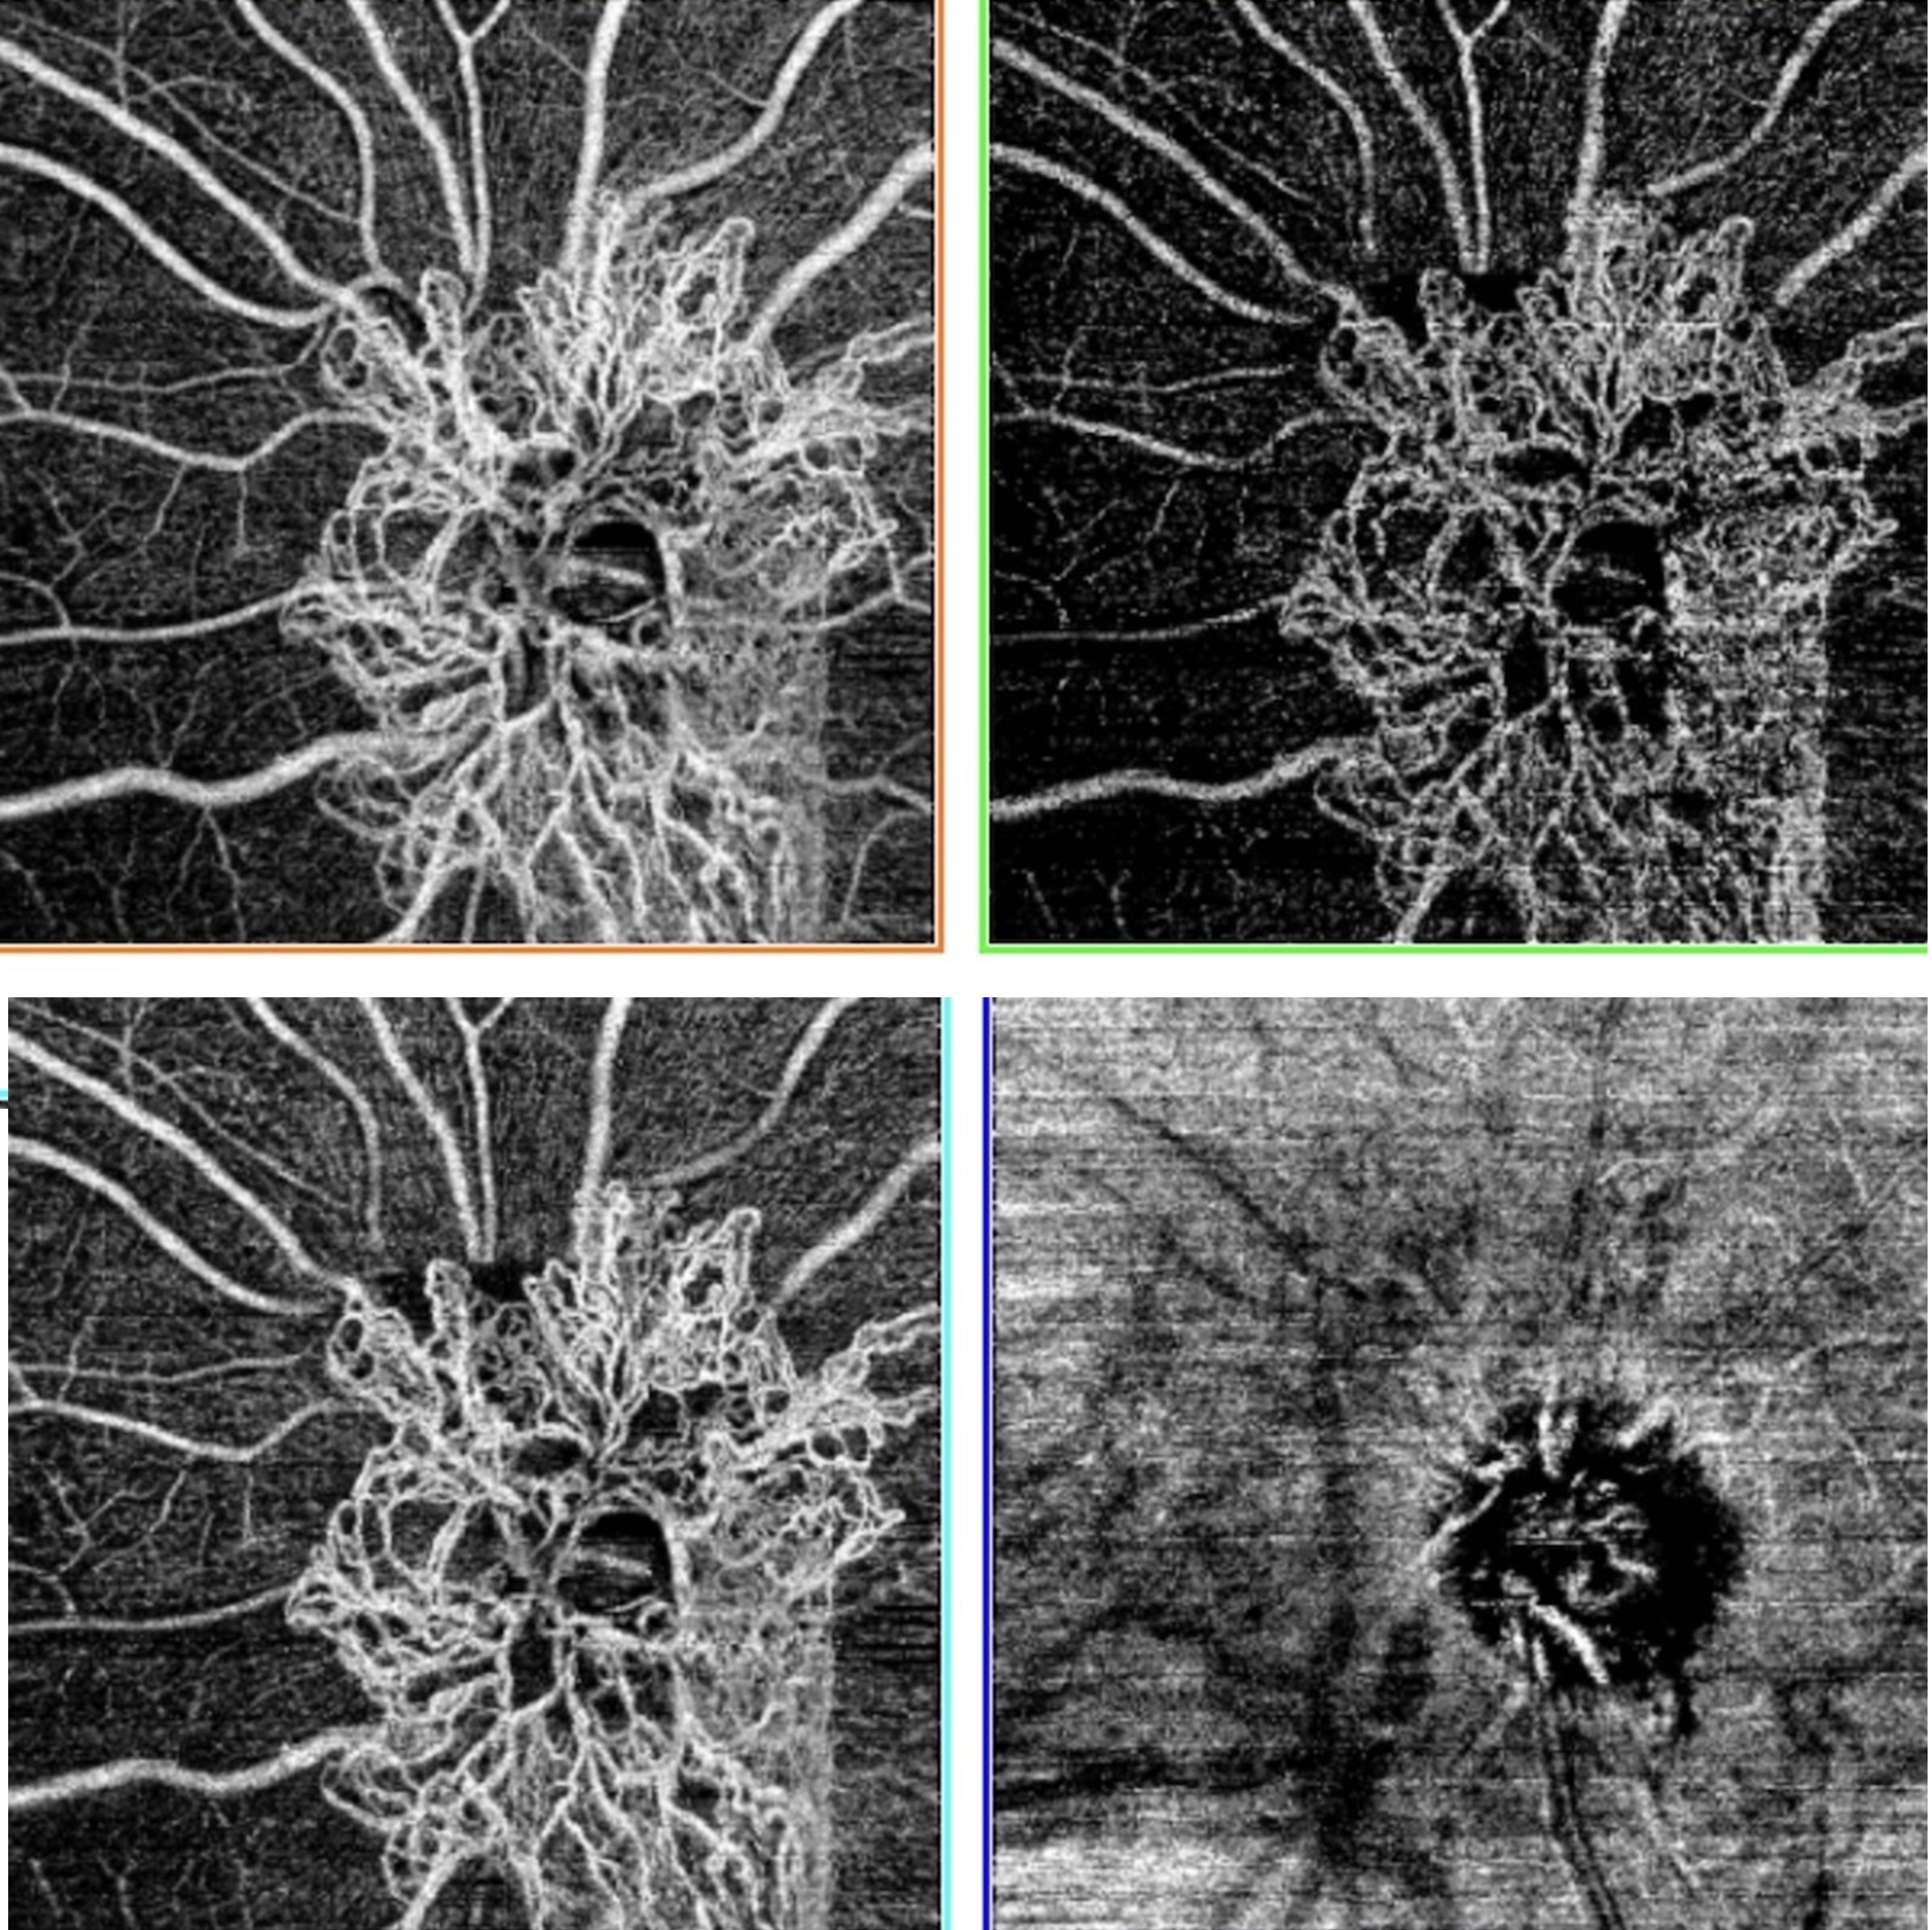

Background: Retinal diseases, including neovascular age-related macular degeneration, diabetic retinopathy, and retinal vein occlusion, are leading causes of vision loss worldwide. The introduction of anti-vascular endothelial growth factor (anti-VEGF) therapies has dramatically changed the management of these conditions, offering targeted treatment that can preserve and even improve vision. We aimed to provide a comprehensive review of the development, clinical applications, and emerging indications of anti-VEGF therapies in ophthalmology, including biosimilar agents.

Results: Anti-VEGF agents have transformed the management of retinal diseases such as neovascular age-related macular degeneration, diabetic macular edema, proliferative diabetic retinopathy, retinal vein occlusion, and retinopathy of prematurity. Newer agents such as brolucizumab and faricimab offer prolonged durability and enhanced anatomic outcomes, while biosimilars provide cost-effective alternatives. Anti-VEGF therapy has also shown promise in off-label or emerging indications such as neovascular glaucoma, corneal neovascularization, and other retinal or choroidal disorders including secondary macular edema and/or macular neovascularization associated with various forms of uveitis, diffuse choroidal hemangioma in Sturge-Weber Syndrome, hereditary retinal disorders such as fundus flavimaculatus, Coats-Like retinitis pigmentosa, Peripherin-2-associated retinopathy, immune checkpoint inhibitor use, radiation retinopathy, retinitis pigmentosa, Bietti crystalline dystrophy, autosomal recessive bestrophinopathy, melanocytoma-associated macular neovascular membrane, Best disease, Wyburn-Mason syndrome, choroidal osteoma, peripheral exudative hemorrhagic chorioretinopathy, traumatic choroidal rupture, torpedo maculopathy, optic disc melanocytoma, type 2 proliferative macular telangiectasia, and Coats disease. High-dose formulations and innovative delivery systems are under active investigation to reduce the treatment burden and extend dosing intervals.